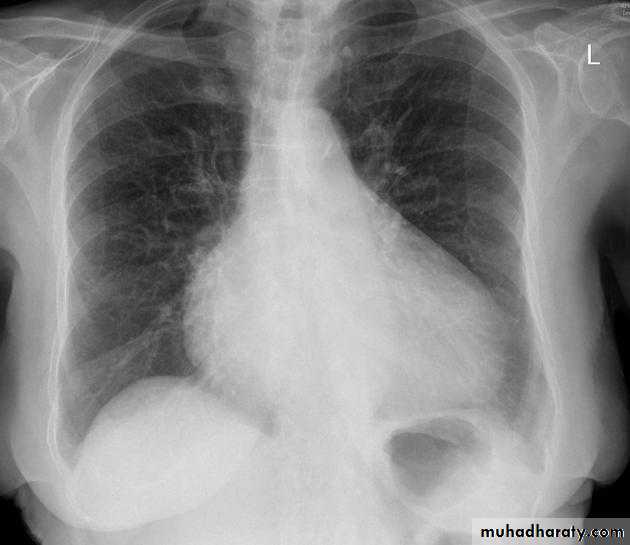

Cardiothoracic ratio (CTR) = Cardiac Width : Thoracic Width

A CTR of greater than 1:2 (50%) is considered abnormal. This however, assumes the projection is Posterior-Anterior (PA), and that cardiac size is not exaggerated by factors such as patient rotation or an incomplete breath in .

The cardiothoracic ratio aids in the detection of cardiomegaly, or more broadly, enlargement of the cardiac silhouette. .

Enlargement of the cardiac silhouette on chest x-ray can be due to a number of causes :

1.cardiomegaly (most common cause by far)2.pericardial effusion

3.anterior mediastinal mass

4.prominent epicardial fat pad